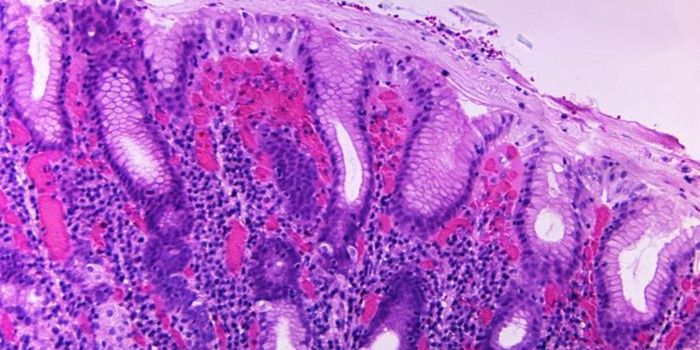

DEC 28, 2021ImmunologyAncylostoma caninum, a type of hookworm, attached to the intestinal mucosa. Image via Wikimedia Commons. Hookworms are b ...